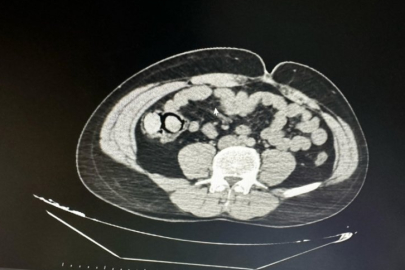

Bingöl'de akıllara durgunluk veren bir olay gerçekleşti. Otobüs yolculuğu sırasında polis ekiplerince durdurulan yabancı uyruklu iki şahsın midesinden 10 parça halinde 113 gram metamfetamin çıktı.

Bingöl Emniyet Müdürlüğü Narkotik Suçlarla Mücadele Şube Müdürlüğüne bağlı narko-timleri akıllara durgunluk veren bir uyuşturucu kaçakçılığını çözdü. Ekiplerin çalışmaları neticesinde otobüs ile Bingöl'e gelen şüpheli yabancı uyruklu 2 şahsın iç beden muayenesinde 10 parça halinde 113 gram metamfetamin maddesi tespit edildi. Emniyetteki işlemlerinin ardından mahkemeye çıkarılan 2 şahıs, uyuşturucu madde ticareti yapmak suçundan tutuklanarak Elazığ Kapalı ceza infaz kurumuna teslim edildi.